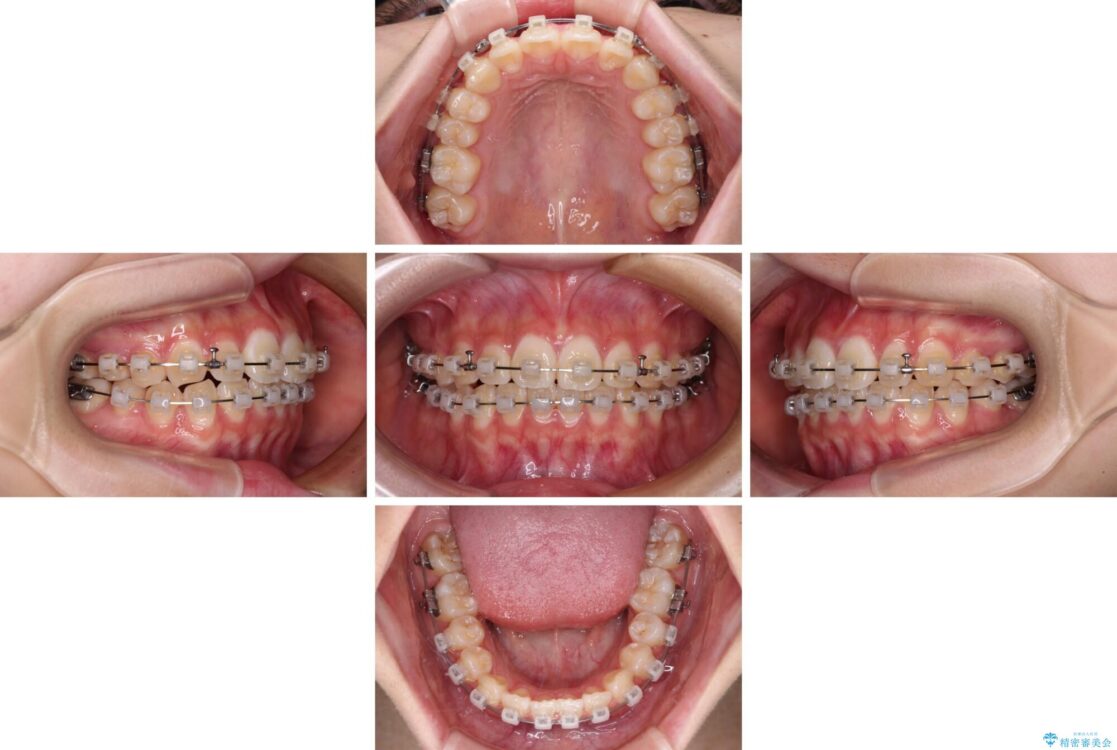

治療途中

• インビザラインは使える自信がない ワイヤー装置にて矯正治療 治療途中画像